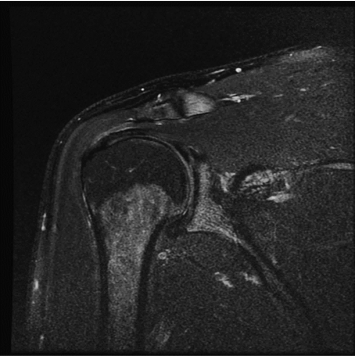

standard

384 x 256 (4 NEX)

3:02 minIAI (Innovative AI)

384 x 256 (2 NEX)

1:30 minReduced Scan Time